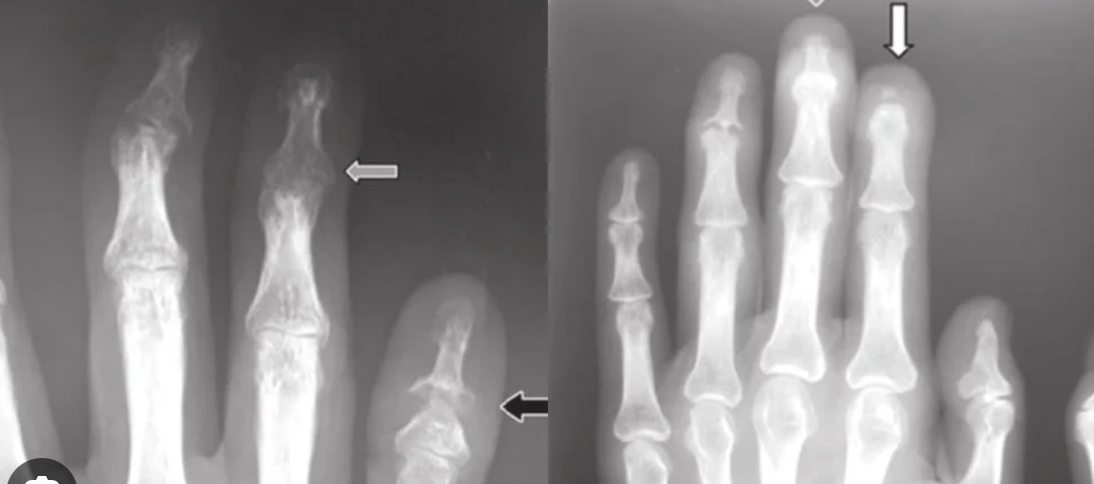

Describe clinical imaging of PsA?

X-ray of affected joints:

- may show erosion of the small joints. Classic findings are erosions of the DIP with periarticular bone formation (osteophytes). In advanced disease, there may be “pencil in cup deformity” at the DIP

X-ray of the sacroiliac joints (SIJ):

- usually normal in the initial stages, but it is important to obtain a baseline radiograph for assessing disease progression

- Periostitis (inflammation of the periosteum, causing a thickened and irregular outline of the bone)

MRI of SIJ:

- looking for joint oedema (not routinely performed due to low specificity)

TOMTIP: The classic x-ray finding in the digits is a “pencil-in-cup” appearance.